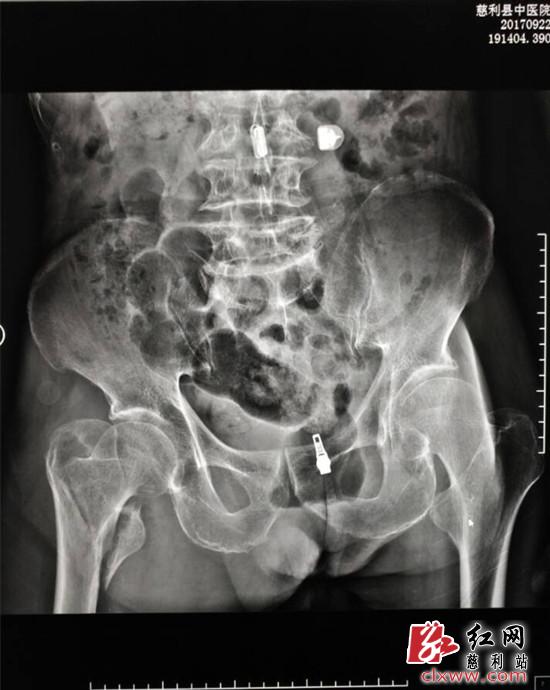

(术前)

9月中旬一天,90岁老人王恩象在行走过程中不慎摔跤,当时感觉大腿右侧疼痛难忍,家人紧急将他送往慈利县中医医院,经诊断为右侧股骨粗隆间粉碎性骨折,需要进行防旋股骨近端髓内钉术(PFNA)。